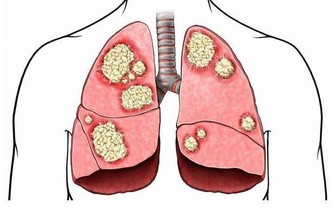

從醫學上來看,肺炎是一種肺部感染,它會導致肺泡出現膿液,使患者出現嚴重的呼吸困難或呼吸衰竭,進而引起死亡。肺炎屬於下呼吸道感染類疾病,根據世界衛生組織統計表明,這類疾病在每年導致全球約有200-300萬人死亡,位列人類死亡原因前五位。